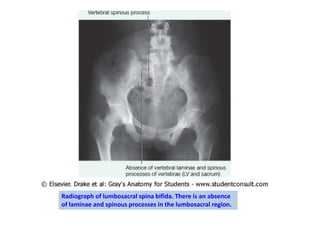

Radiograph of lumbosacral spina bifida. There is an absence

of laminae and spinous processes in the lumbosacral region.